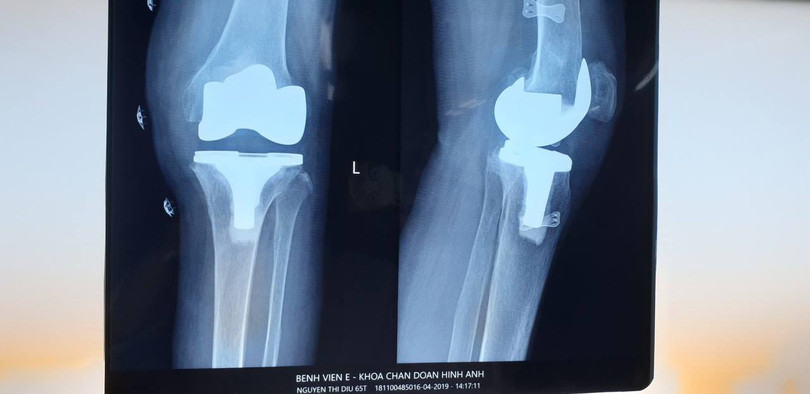

| Ảnh chụp Xquang khớp gối của bệnh nhân |

“Chân bệnh nhân co rút, gấp hơn 30 độ nên rất khó phẫu thuật. Bên cạnh đó, các triệu chứng thoái hóa khớp gối cho thấy bệnh nhân đã bị tổn thương sụn khớp nghiêm trọng. Khớp sưng đau cản trở việc vận động của bệnh nhân, khiến có thể dần bị mất hoàn toàn chức năng vận động” – Bác sĩ Hiền cho biết.

Thể trạng bệnh nhân gầy yếu, nguy cơ biến chứng cao, tỷ lệ thành công thấp, nên việc phẫu thuật đòi hỏi bác sĩ phải thực hiện các kỹ thuật cao, thao tác chính xác.

Tuy nhiên, các bác sĩ vẫn quyết tâm phẫu thuật cho bệnh nhân. Sau 2 giờ tiến hành ca mổ, bệnh nhân được thay khớp gối toàn phẩn. Sau 1 tuần, bệnh nhân đã tập đi trở lại và có thể sớm xuất viện.